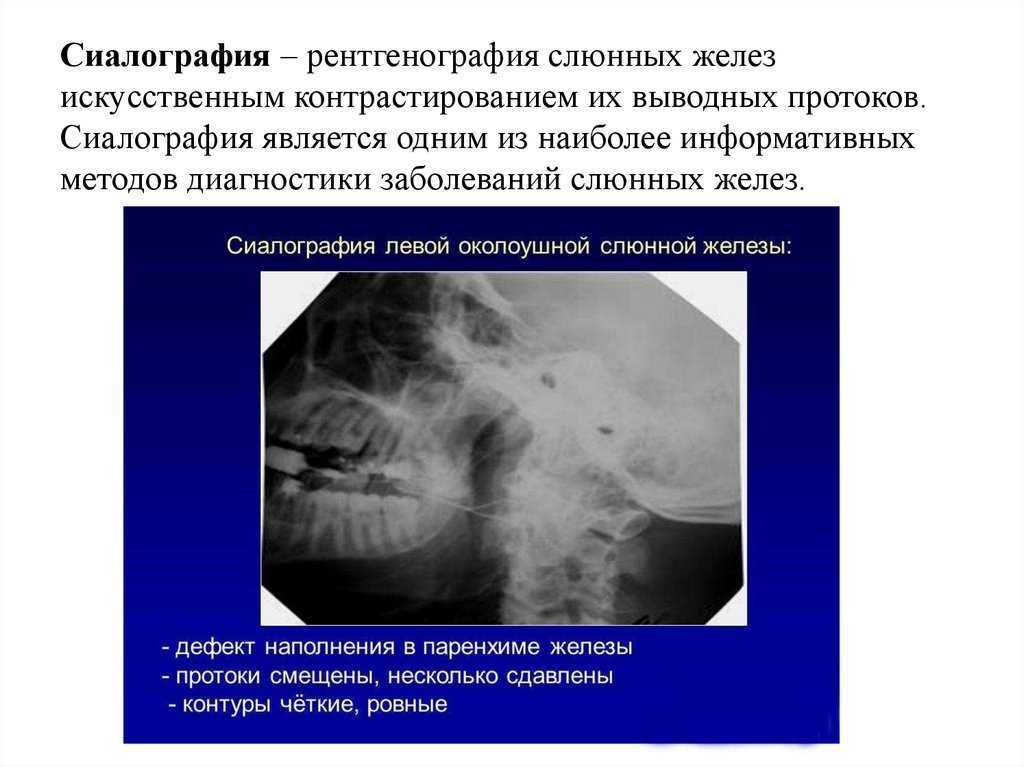

Маммография косая проекция укладка. Маммография молочных желез. Маммография это исследование. Рентгеновская маммография. Подчелюстная слюнная железа на рентгене. Сиалография слюнных желез. Рентгенография слюнных желез. Контрастная сиалография слюнных желез.

Подчелюстная слюнная железа на рентгене. Сиалография слюнных желез. Рентгенография слюнных желез. Контрастная сиалография слюнных желез. Фиброаденома молочной железы дифференциальный диагноз. Новообразование молочной железы фиброаденома. Диф диагноз фиброаденомы молочной железы. Фиброаденома молочной железы 30мм-37мм.